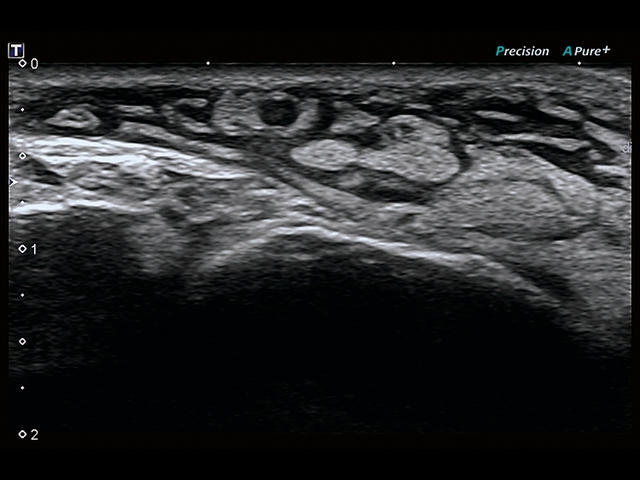

Обновленная версия легендарного УЗ-сканера. Стационарный аппарат экспертного класса Aplio 500 Toshiba NEW, визуализирует анатомические структуры в высоком разрешении. Модель позволяет выявить микрокальцификаты, новообразования, нарушения в работе сердца, сосудов и мышц. Присутствует функция виртуальной эндоскопии, 4D-сканирования, эластометрии тканей, УЗИ с контрастированием. За повышение качества изображения отвечают технологии ApliPure и Superb Microvascular Imaging. Первая задействует возможности пространственного и частотного кодирования, формирует цельный визуальный ряд с сохранением клинических маркеров. Вторая улучшает отображение микрососудистого русла, используя доплеровский эффект. Модель оснащена 21-дюймовым монитором, имеет 4 активных порта. Возможно подключение педиатрических, интраоперационных, лапароскопических и чреспищеводных датчиков.

• SMI. Опция, упрощающая визуализацию микроциркуляторного русла. С ее помощью обследуются сосуды с низкой интенсивностью кровотока, изучаются наиболее тонкие структуры. SMI упрощает диагностику новообразований, минимизирует вероятность ошибки.